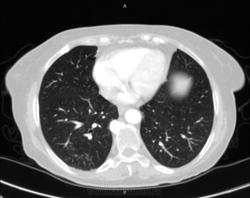

Метастазы по брюшине, сальнику -  моё мнение. Откуда - я не знаю. Возможно, первичная опухоль в селезенке (дифференцировать между гемангиосаркомой и метастазом). Но более реально - из яичников или молочных желез. Одни вопросы, поскольку полость таза не вошла в зону сканирования. Изменения в легких - тоже в срезе.